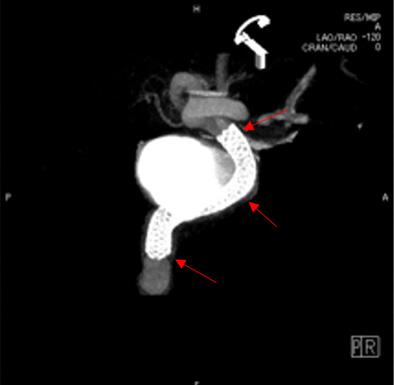

脳ドックで未破裂脳動脈瘤を指摘され、当院にご紹介いただき血管内治療を行いました。

いずれの症例も、半年後の検査で脳動脈瘤が完全に閉塞しています。

内頸動脈瘤(青矢印)にPIPELINE(フローダイバーターステント:赤矢印)を留置

椎骨動脈瘤(青矢印)にFRED(フローダイバーターステント:赤矢印)を留置